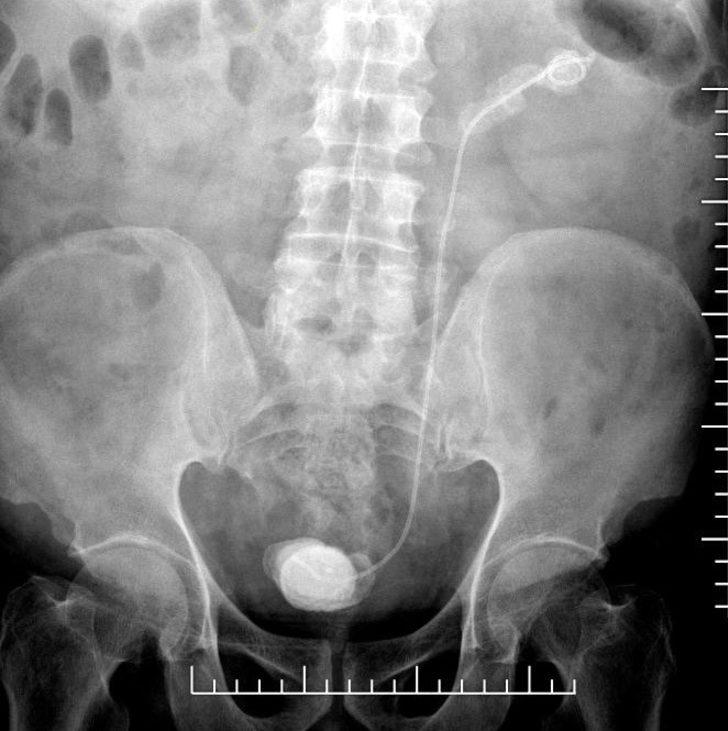

Dr. Yıldırım'ın hastaya sorması üzerine Elban’ın 7 sene önce Ankara’da bir hastanede bağırsaklarından ameliyat olduğu ve stent takıldığı öğrenildi. Bunun üzerine Op. Dr. Yıldırım tarafından yapılan operasyonla unutulan stent ve etrafındaki taşlar alındı.

Hastanın 7 yıl önce bağırsak operasyonu geçirdiğini belirten Op. Dr. Kadir Yıldırım, “Bu işlem sırasında DJS stent uygulanıyor ve 1 ay içerisinde alınması gerekiyor. Bu stent bazen hekim veya hasta kaynaklı unutulabiliyor. Bu hastamızda da böyle bir talihsizlik olmuş.

7 yıl boyunca böbrekte ve kanalında kalmış. Bu süre zarfında böbreklerde ileri boyutta taşlaşma olabiliyor. Bu tür durumlarla dünyada ve ülkemizde karşılaşılabiliyor. Bu hastanın tedavisinde endoskopik ameliyatlar dizisi ile tek seansta taşsızlık sağladık ve stendi çıkardık.

İlk başta böbrek kanalındaki taşlar lazer ve pnömotik litotriptör (havalı sistem ile taş kırma işlemi) ile kırıldı. Takiben böbrek üst polündeki 7 santimlik taş, fleksibl renoskop ile kırıldı” dedi.

Mesanede de 8 santimlik bir taşın oluştuğuna değinen Op. Dr. Yıldırım, “Bunu küçük bir kesi ile çıkardık. Hastamızın genel durumu iyi ve takiplerimize devam ediyoruz. 7 yıl çok ciddi bir süre. Aslında 1 yıl bile geç denilecek bir zaman ama 7 yıl kalmış.